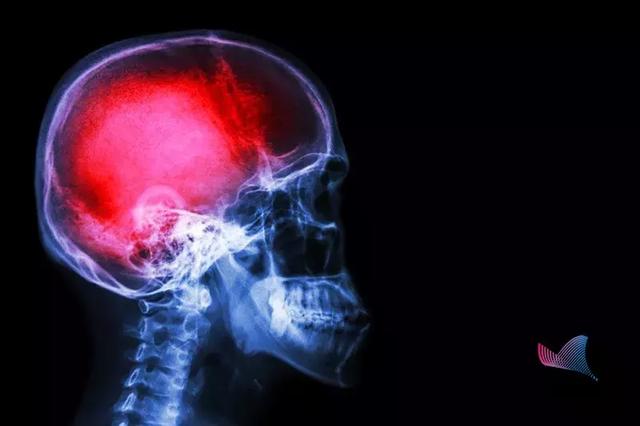

中國人死亡原因榜:世界頂級醫(yī)學(xué)期刊《柳葉刀》發(fā)表中國人死亡原因排行榜,從1990年到2017年,排在第一位的是腦中風(fēng)。中國男性的中風(fēng)發(fā)病風(fēng)險(xiǎn)也是全球男性中最高的,超過了41%。很多研究都指出高鈉攝入是重要因素,簡單來說就是中國人鹽吃多了,所以,尤其警惕,重口味的人更容易得腦中風(fēng)。

中風(fēng)

第一殺手,是造成中國人壽命損失的第一大病因。據(jù)WHO數(shù)據(jù)顯示,我國腦卒中的發(fā)生率位居世界第一。

我國每年腦卒中發(fā)生病例500余萬,其中約有196萬人死亡。

也就是說,

腦卒中

每6.2秒就有一人發(fā)生,每16秒就有一人死亡!腦卒中已成為我國居民死亡首要因素。更可怕的是,中風(fēng)不僅僅是老年人的專利,在我國

腦卒中,又稱中風(fēng),很多人對中風(fēng)的認(rèn)識(shí)只是停留在患者會(huì)口眼歪斜、口齒不清。

當(dāng)附著在血管壁的栓子脫落,堵塞腦部血管時(shí),形成缺血性中風(fēng)。而當(dāng)腦血管破裂,顱內(nèi)出血時(shí),就會(huì)形成出血性中風(fēng)。